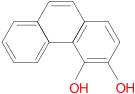

Structures

| Morphides | ||||

|---|---|---|---|---|

Codeine Codeine |

Morphine Morphine |

Oripavine Oripavine |

Pseudomorphine Pseudomorphine |

Thebaine Thebaine |